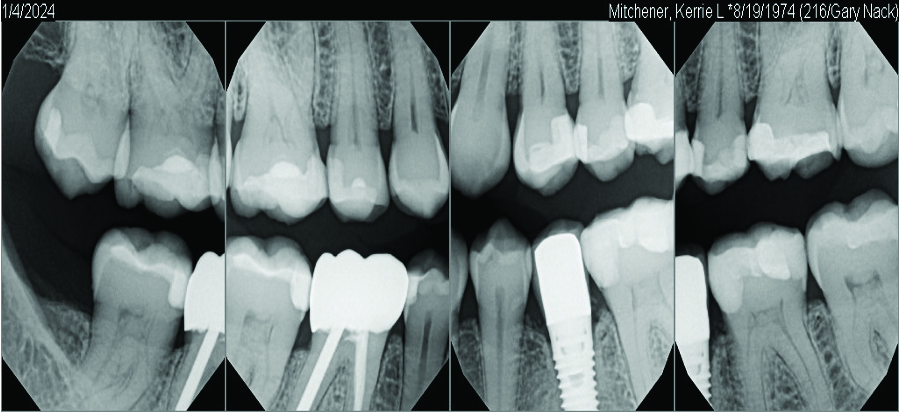

At 5 years post-implant placement, implant site No. 20 showed circumferential depths of 6 mm to 8 mm with heavy bleeding on probing (Figure 1).1,47 The keratinized mucosa width locally recorded 4 mm buccally and lingually, with a thick gingival phenotype. The four-wall intrabony lesion was diagnosed as a class 1c (circumferential) intrabony peri-implant defect with less than 40% defect angulation in the mesial and distal radiographic aspects (Figure 2).48 Additionally, resin cement-associated peri-implantitis was diagnosed.49 The patient preferred to maintain the existing well-fitting crown due to financial concerns. The patient would be considered low-medium risk according to the PIDRA (Table 3). (To view Table 3, the PIDRA for this case, visit compendiumce.com/go/2505.)

A postsurgical periapical x-ray was taken (Figure 9). Postoperative visits were at 2- to 3-week intervals. The patient was instructed to use chlorhexidine for 2 weeks, followed by the use of a two-row soft toothbrush and interproximal flossing. Interproximal proxy brush usage began after the suture removal at 4 weeks. After 2 months, healing was excellent (Figure 10); at 9 months, the interproximal papillae regeneration was complete, and radiographic confirmation of radiographic intrabony defect fill was observed (Figure 11 and Figure 12). After 1 year, maintenance visits were conducted by the restorative office's registered dental hygienist.

Six-year and 11-year recall visits (Figure 13 through Figure 15) confirmed stable long-term soft- and hard-tissue regeneration and bone healing.

Fig 2. A radiograph of the dental implant area before treatment depicted the defect angle, which was less than 40%.

Figure 2

Fig 13. Radiograph at 6-year recall.

Figure 13

Fig 15. Bitewing series at 11-year follow-up showing stable bone levels. (Periodontist: Robert A. Levine, DDS; Restorative dentist: Gary Nack, DDS)

Figure 15